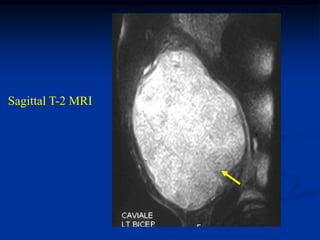

Case #1203 61 yearmale with pleomorphic liposarcoma biceps muscle Sagittal T-1 MRI

• 260.